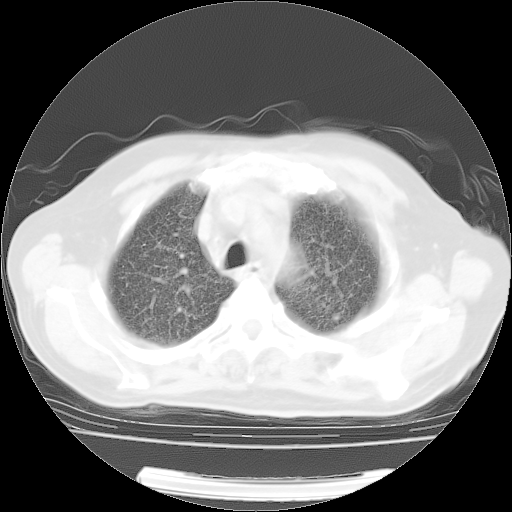

4月14日肺部CT